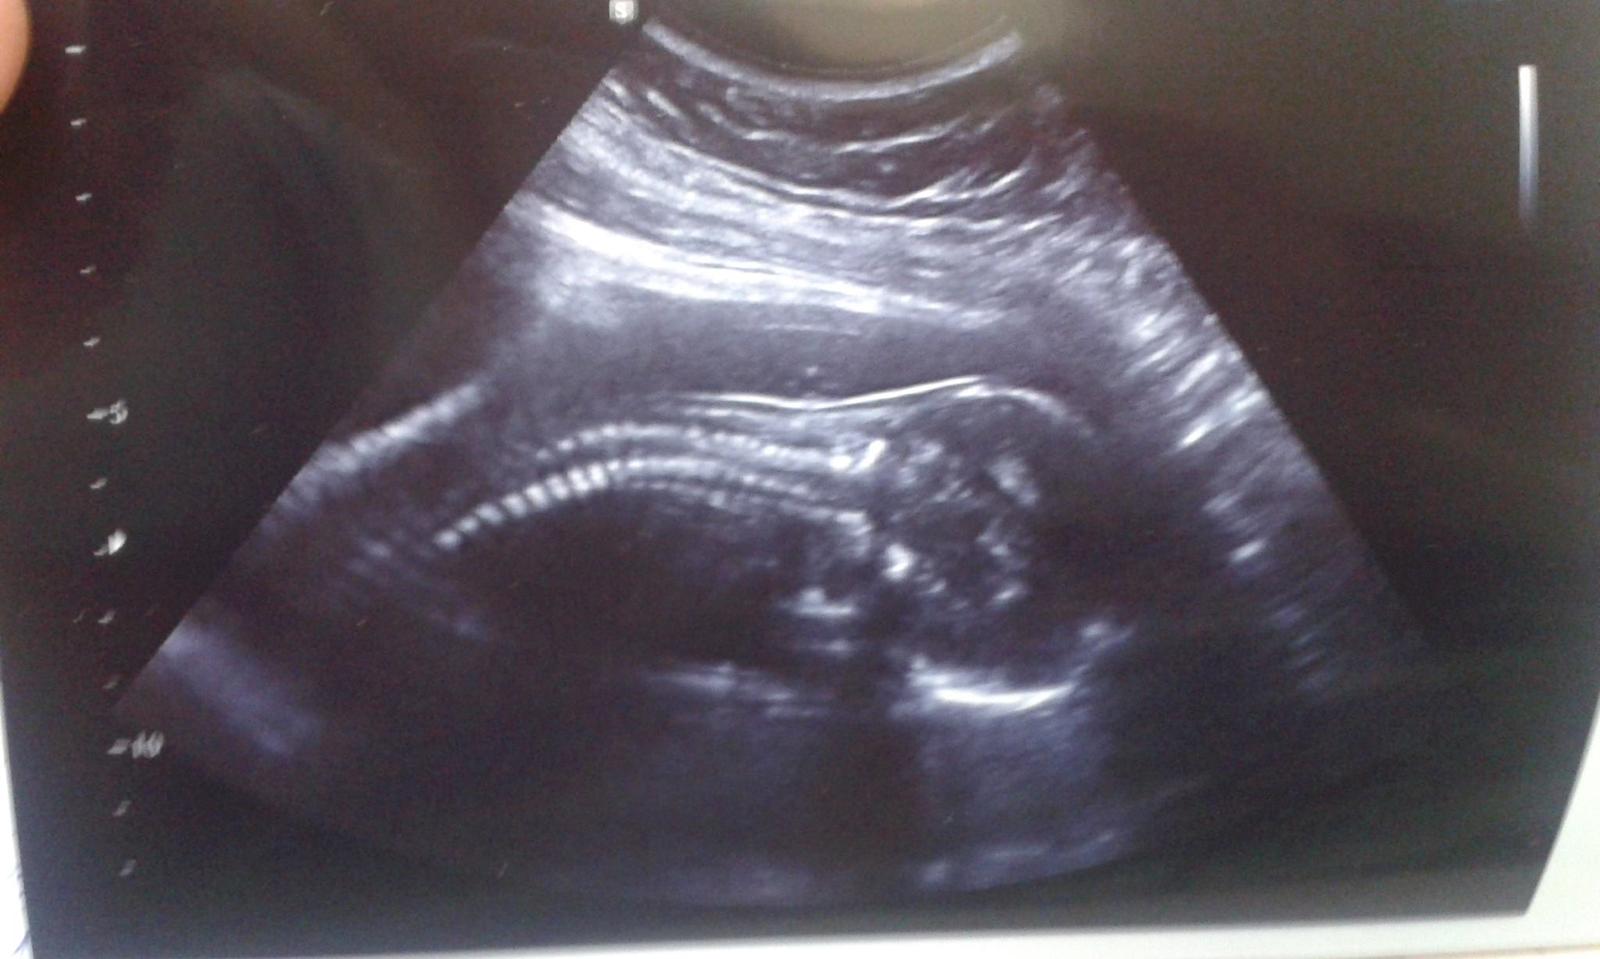

18+4 utz a jsem kluk... mé jméno Richard